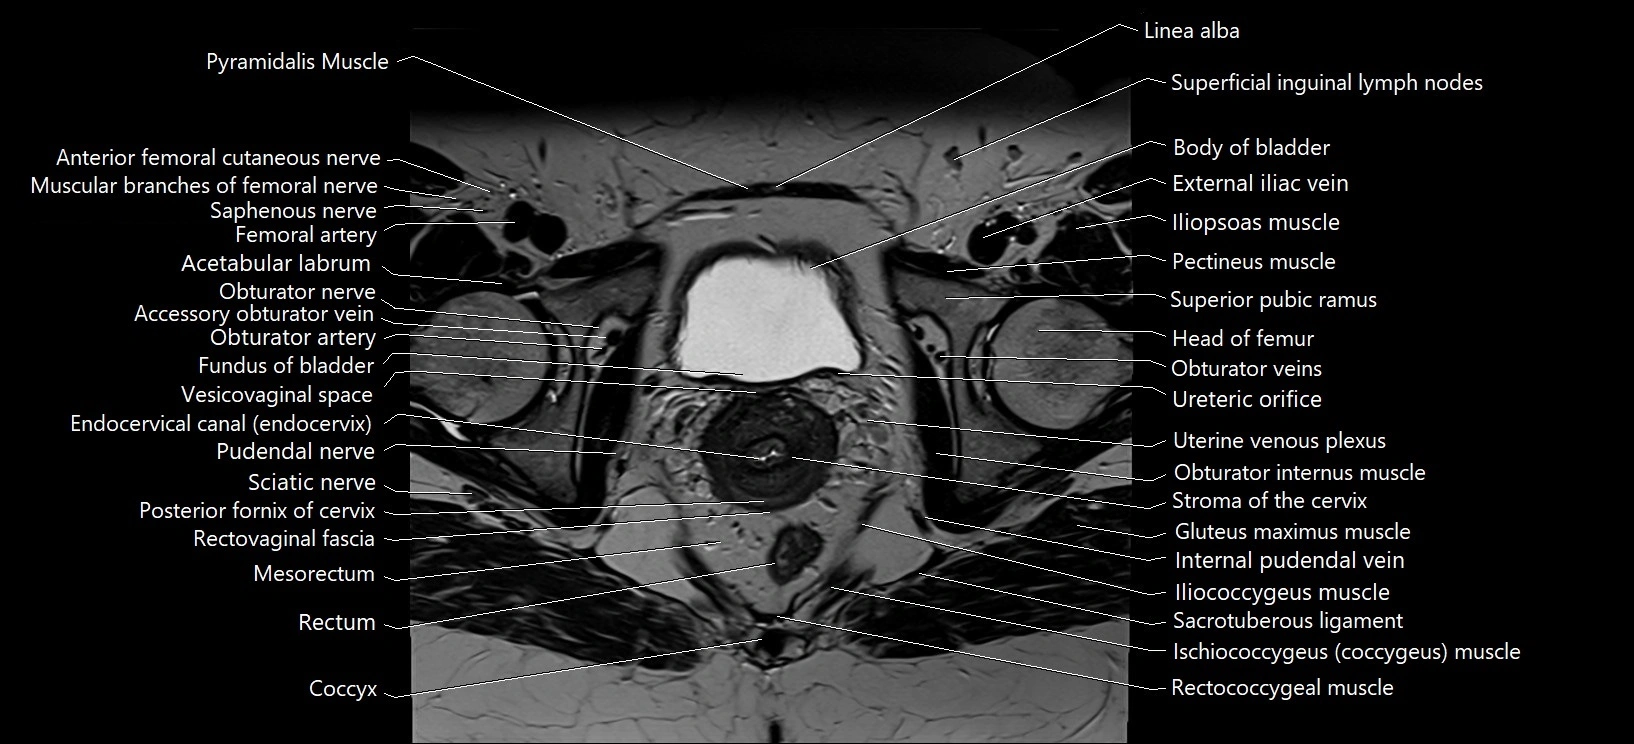

- Acetabular labrum

- Acetabulum

- Body of urinary bladder

- Coccyx

- Endocervical canal

- External iliac vein

- Fundus of urinary bladder

- Head of femur

- Iliococcygeus muscle

- Iliopsoas muscle

- Iliopsoas tendon

- Internal pudendal vein

- Ischiococcygeus muscle

- Linea alba

- Median umbilical ligament

- Mesorectal fascia

- Mesorectum

- Obturator externus muscle

- Obturator internus muscle

- Obturator nerve

- Obturator veins

- Pectineus muscle

- Posterior fornix of cervix

- Pudendal nerve

- Pyramidal muscle (pyramidalis muscle)

- Rectovaginal septum (rectovaginal fascia)

- Rectum

- Sacrotuberous ligament

- Sciatic nerve

- Stroma of the cervix

- Superficial inguinal lymph nodes

- Superior pubic ramus

- Ureteric Orifice

- Uterine venous plexus